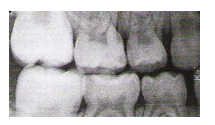

A técnica radiográfica de eleição para a visualização de processos cariosos em coroas dentais superiores e inferiores, bem como a visualização das cristas alveolares, denomina-se: